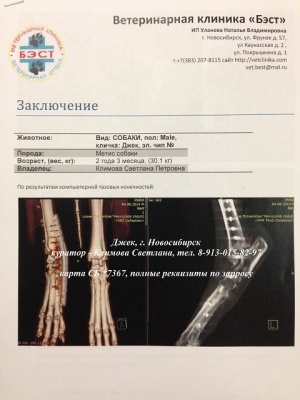

– предоплата за проведение компьютерной томографии правого скакательного сустава (КТ) врач Горшков Сергей Сергеевич, и операции (снятие пластины) хирург Козлов Евгений Матвеевич, клиника Бэст (чек 1, заключение КТ – документ 1, лист назначений – документ 1-1) – 5000 руб.;

– окончательная оплата за проведение компьютерной томографии правого скакательного сустава (КТ) врач Горшков Сергей Сергеевич, и операции (снятие пластины) хирург Козлов Евгений Матвеевич, клиника Бэст (чек 3, товарный чек 3, лист назначений – документ 3) – 7756 руб.;

– предоплата за проведение компьютерной томографии правого скакательного сустава (КТ) врач Горшков Сергей Сергеевич, и операции (снятие пластины) хирург Козлов Евгений Матвеевич, клиника Бэст (чек 1, заключение КТ – документ 1, лист назначений – документ 1-1) – 5000 руб.;

– окончательная оплата за проведение компьютерной томографии правого скакательного сустава (КТ) врач Горшков Сергей Сергеевич, и операции (снятие пластины) хирург Козлов Евгений Матвеевич, клиника Бэст (чек 3, товарный чек 3, лист назначений – документ 3) – 7756 руб.;